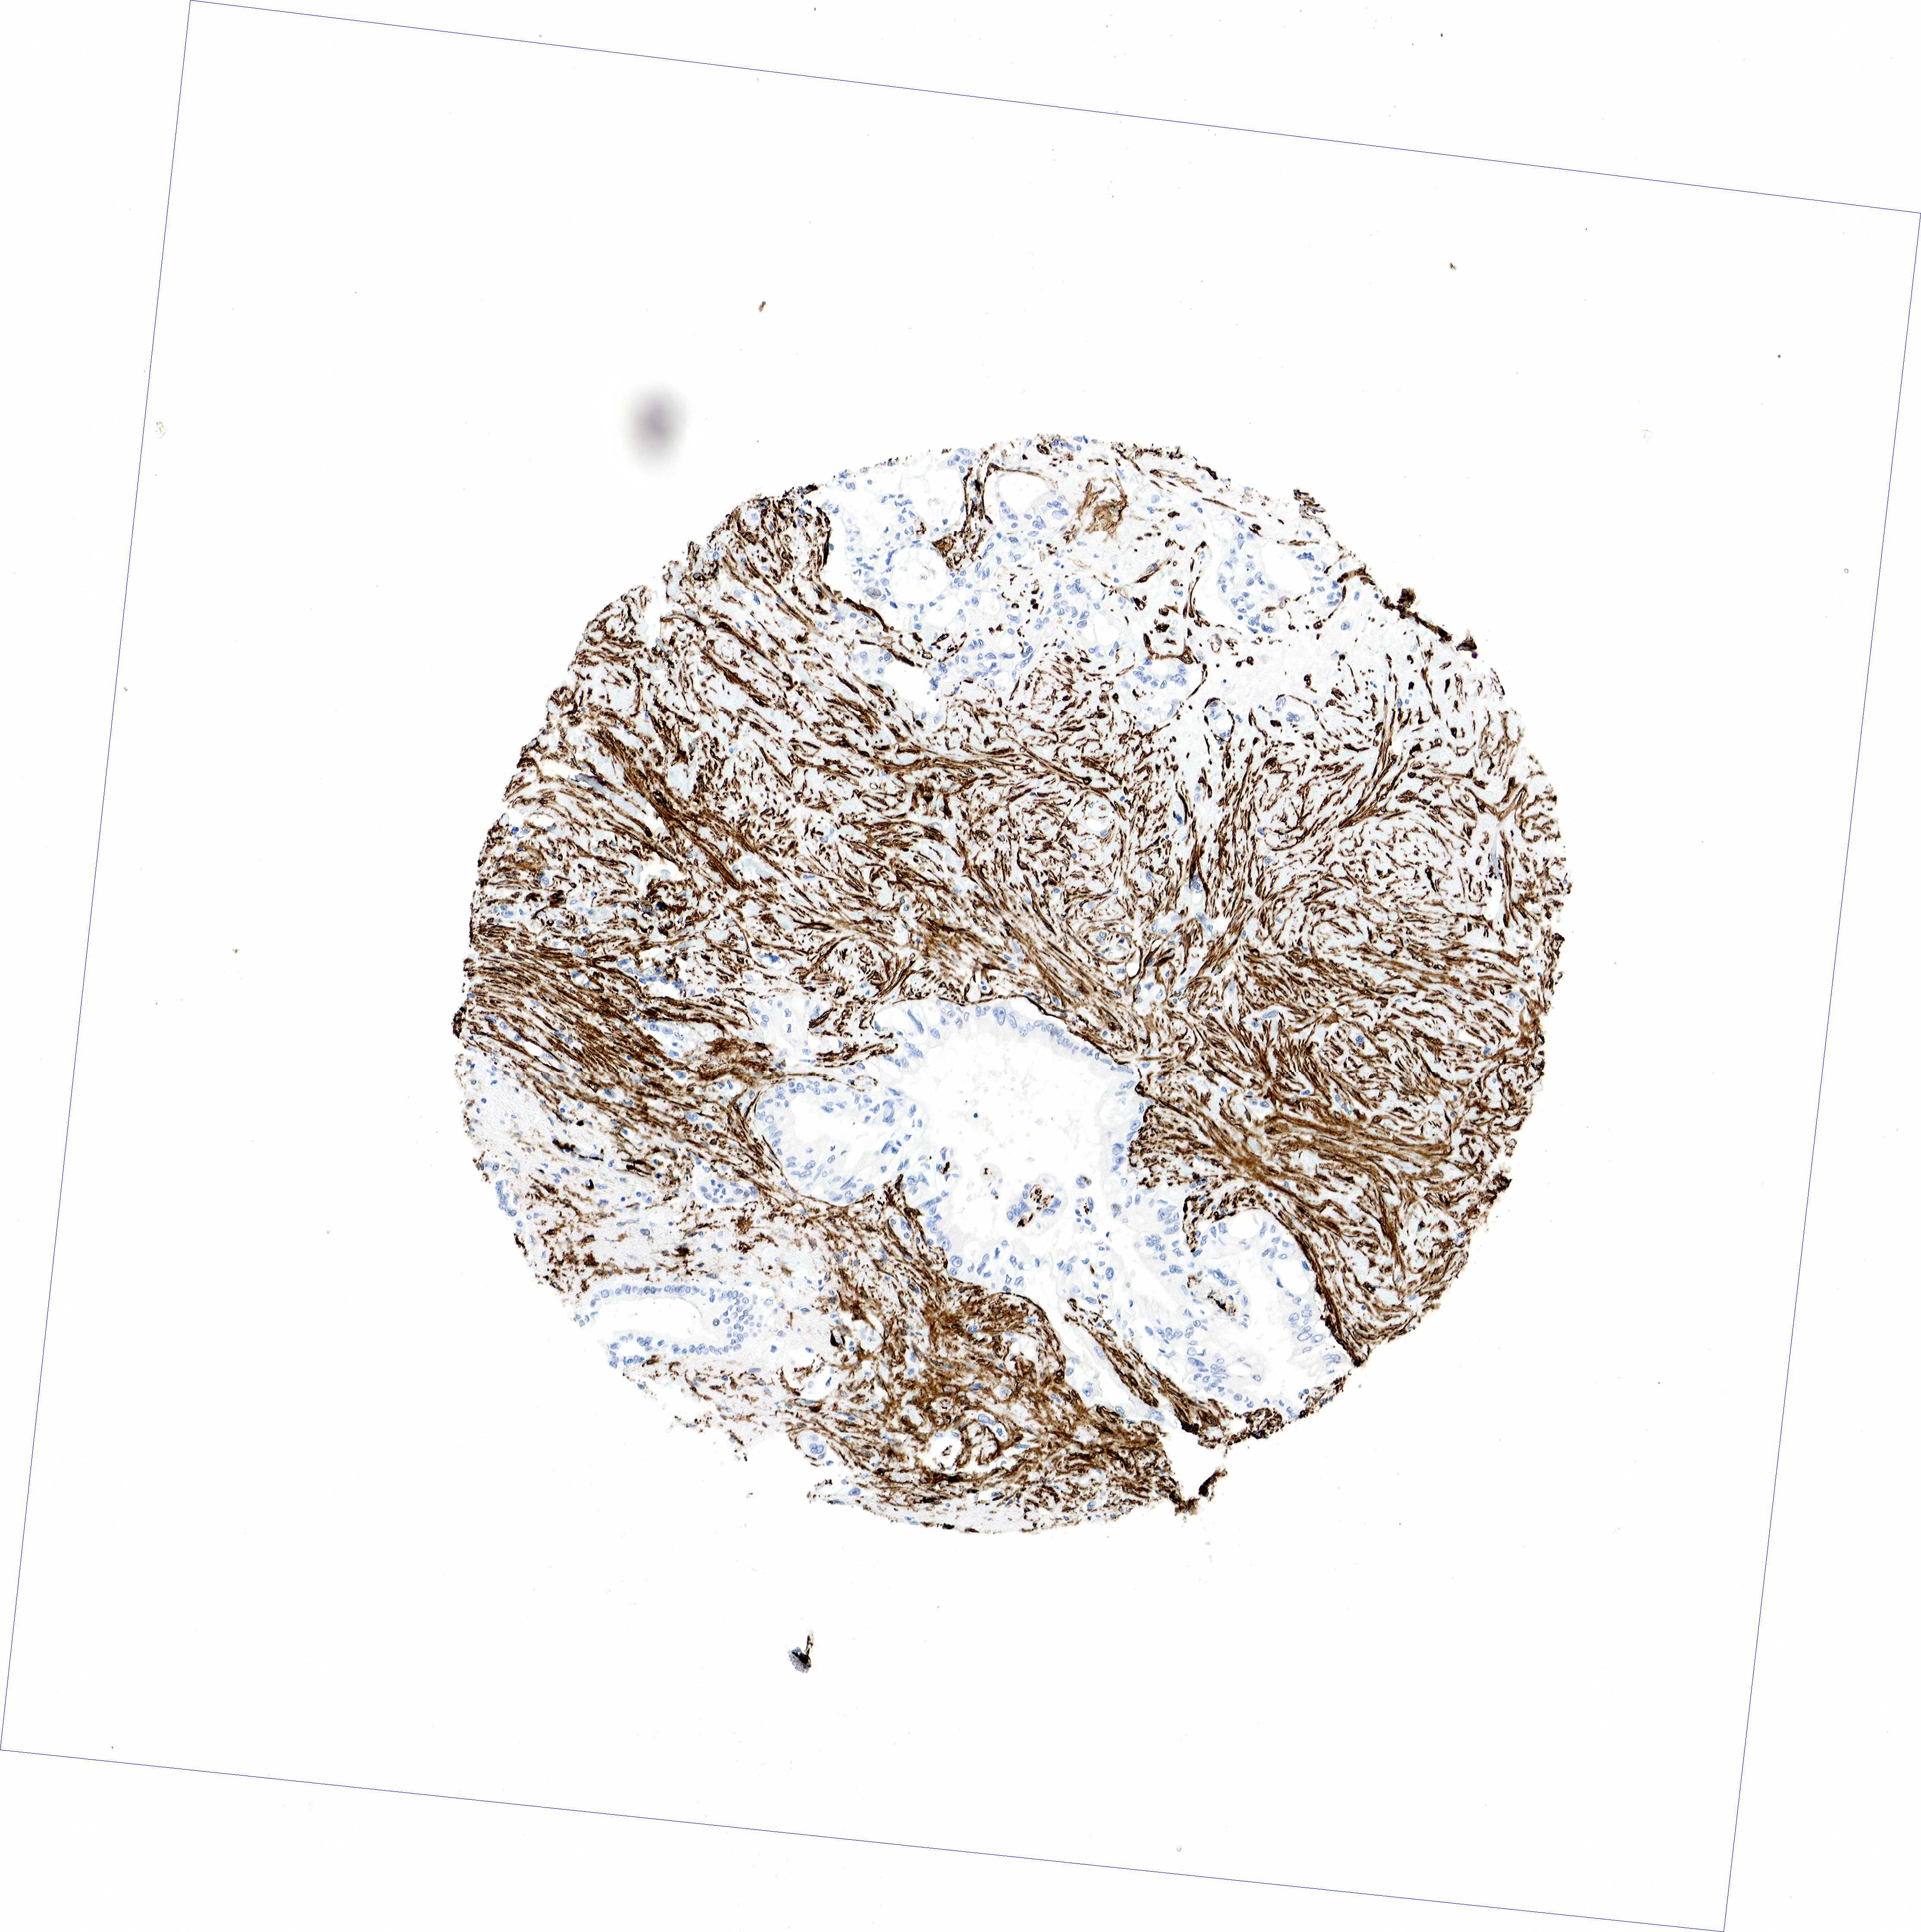

PANCREATIC CANCER - Protein expressioni

A mouse-over function shows sample information and annotation data. Click on an image to view it in a full screen mode. Samples can be filtered based on level of antibody staining by selecting one or several of the following categories: high, medium, low and not detected. The assay and annotation is described here.

Note that samples used for immunohistochemistry by the Human Protein Atlas do not correspond to samples in the TCGA dataset.

Antibody stainingi

Antibody staining in the annotated cell types in the current human tissue is reported as not detected, low, medium, or high, based on conventional immunohistochemistry profiling in selected tissues. This score is based on the combination of the staining intensity and fraction of stained cells.

Each image is clickable and will lead to virtual microscopy that enables deeper exploration of all samples and also displays staining intensity scores, fraction scores and subcellular localization as well as patient and tissue information for each sample.

HPA041264

HPA041271

CAB000002

CAB003761

CAB013531

Staining

High

Medium

Low

Not detected

Intensity

Strong

Moderate

Weak

Negative

Quantity

>75%

75%-25%

<25%

None

Location

Nuclear

Cytoplasmic/membranous

Cytoplasmic/membranous,nuclear

Adenocarcinoma, NOS